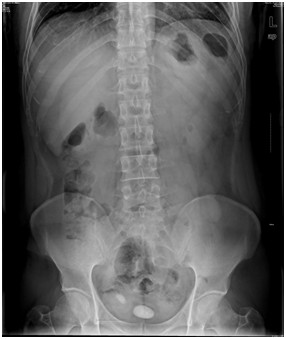

临床实践技能影像诊断模拟试题:某急腹症患者,其腹平片提示